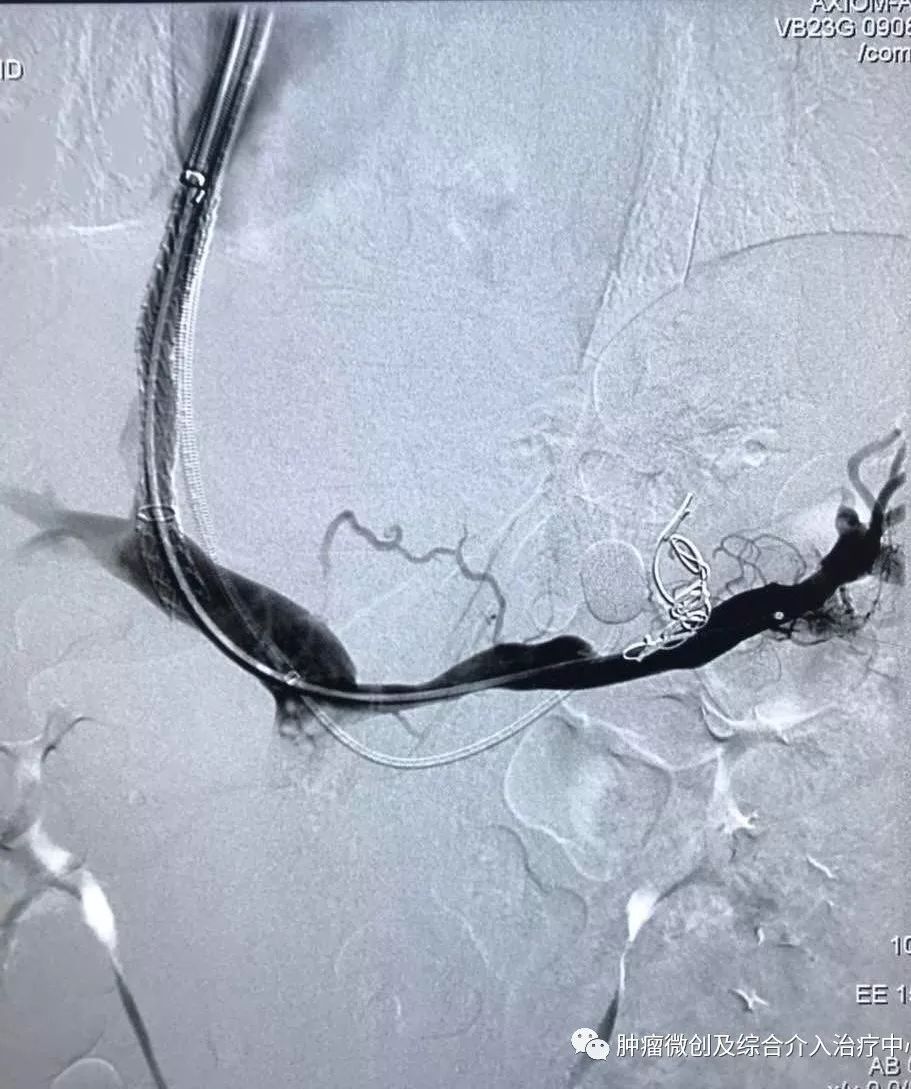

(鼻咽癌颈部转移瘤破溃出血,DSA造影提示左颈部病变血管迂曲、紊乱,内有出血)

(介入栓塞病变血管后,DSA示肿瘤病变血管栓塞好,血管走向清晰,出血停止)项目介绍:头颈部良、恶性肿瘤临床常见,其良性见于鼻咽纤维血管瘤,恶性者见于鼻咽、鼻窦癌,颈部转移性肿瘤等; 传统止血治疗疗效有限,给患者及家属带来极大的精神压力,介入手术栓塞病变血管可达到确切的止血效果,并致病变缺血萎缩。04急性肺栓塞介入手术治疗